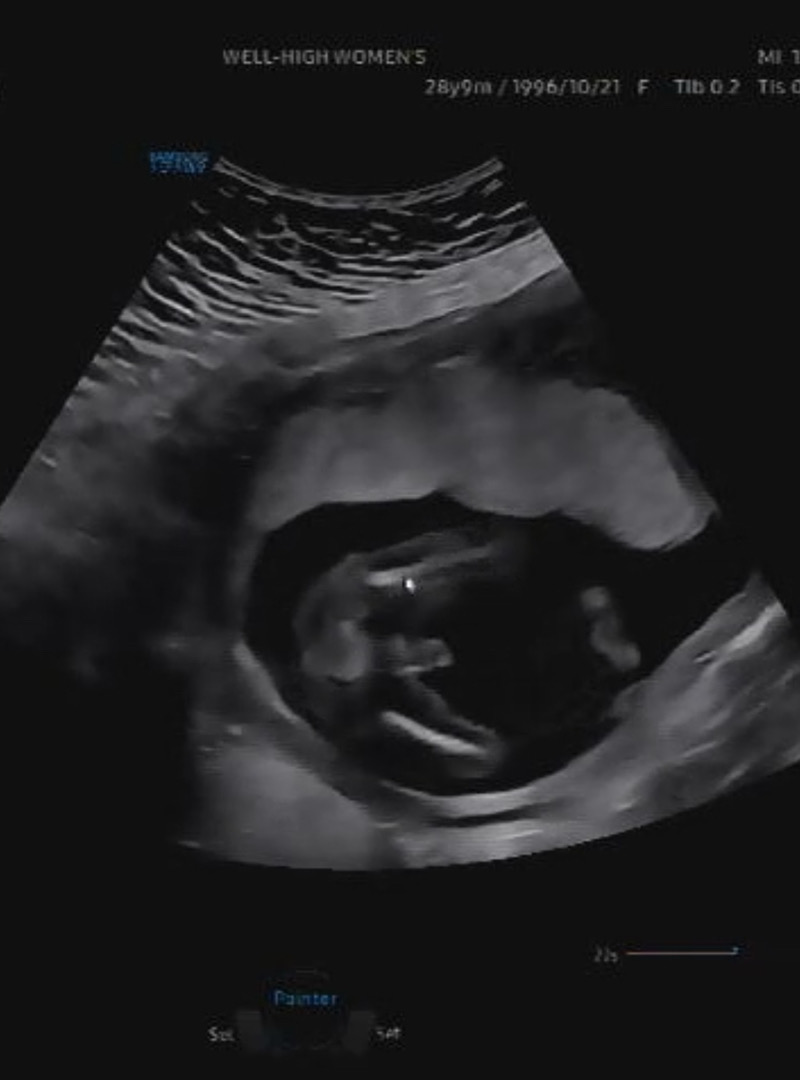

16주차 성별

16주 6일차 이정도면 아들 빼박인거죠 ..?